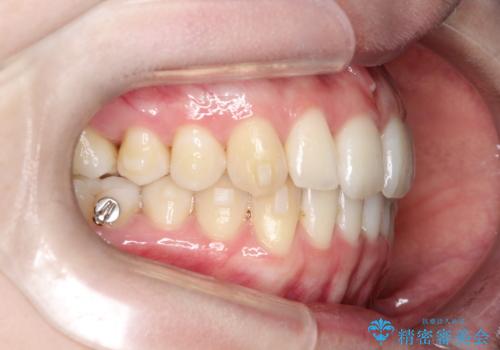

- 患者様は、前歯のガタガタ(叢生)と左下5番の欠損部が気になるとのことで来院されました。診断の結果、インビザラインを用いて前歯の叢生を整えながら、左下5番の欠損部にはインプラント治療を計画しました。矯正治療により、歯並びを改善すると同時に、噛み合わせのバランスも向上させることを目標としました。矯正期間とインプラントの治療計画を並行して進めることで、患者様のご希望に応えるプランを立てました。

前歯の叢生改善のため、インビザラインによる透明で目立たない矯正装置を使用しました。治療中は、歯の移動による負担を最小限に抑えつつ、歯列全体のバランスを考慮して進めました。左下5番の欠損部には、矯正終了後にインプラントを埋入し、自然で機能的な咬合を回復しました。治療期間中、患者様には装置の正しい装着と日々の清掃を徹底していただき、歯肉やインプラント周囲の健康を保つようサポートしました。結果として、美しい歯並びと快適な噛み合わせを両立させることができました。